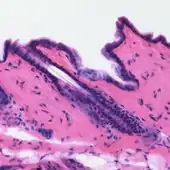

6. This naturally derived dye has been used as a histologic stain, ink[3][4][5][6] and as a dye in the textile and leather industry.[7][8] As a dye, haematoxylin has been called Palo de Campeche,[8] logwood extract,[7] bluewood[9] and blackwood.[9] In histology, haematoxylin staining is commonly followed (counterstained), with eosin,[10][11][1] when paired, this staining procedure is known as H&E staining, and is one of the most commonly used combinations in histology.[1][12][13][7][14] In addition to its use in the H&E stain, haematoxylin is also a component of the Papanicolaou stain (or PAP stain) which is widely used in the study of cytology specimens.[14][1]

Haematoxylin stain is commonly followed (or counterstained) with another histologic stain, eosin.[10][11][1] When paired, this staining procedure is known as H&E staining, and is one of the most commonly used combinations in histology.[1][12][7][14] Haematoxylin is also a component of the Papanicolaou stain (or PAP stain) which is widely used in the study of cytology specimens, notably in the PAP test used to detect cervical cancer.[14][1]

Principally used as a nuclear stain (to stain the cell nucleus), haematoxylin will also stain rough endoplasmic reticulum, ribosomes, collagen, myelin, elastic fibers, and acid mucins.[10] Haematoxylin alone is not an effective stain, but when oxidized to hematein, and combined with a mordant, stains chromatin in cell nuclei dark blue to black.[1][7][25][10] The colour and specificity of haematoxylin stains are controlled by the chemical nature, and amount, of the mordant used, and the pH of the staining solution, thus, a variety of haematoxylin formulations have been developed.[1][10][15]